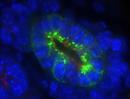

| Immunofluorescence of mutant 012-033-2 (E15.5) ureteric bud with very short cilia | Cplane1b2b012Clo/Cplane1b2b012Clo | C57BL/6J-Cplane1b2b012Clo |